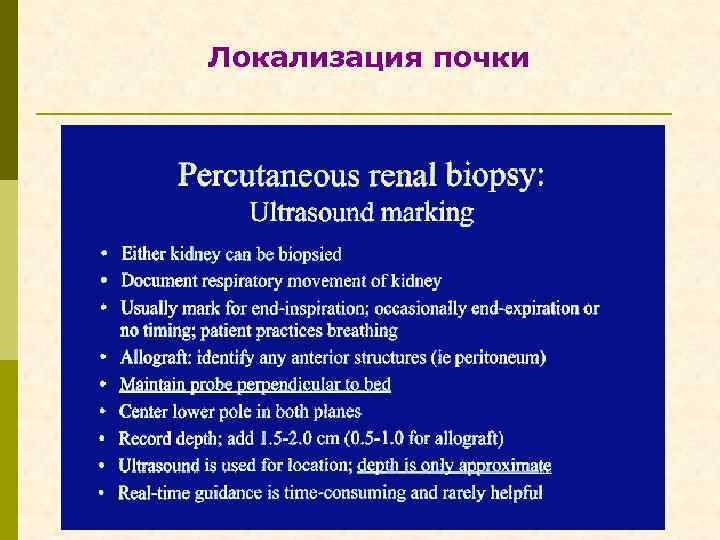

Локализация почки